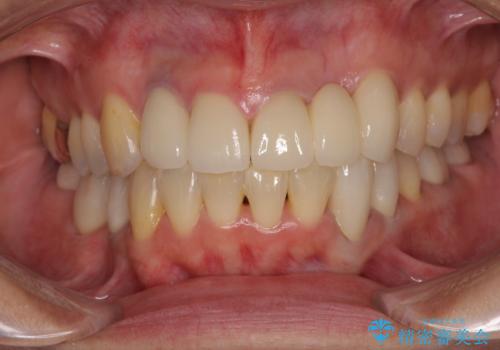

捻れて飛び出した前歯 インビザラインで整った前歯に

- 上下前歯のデコボコと、それに伴う出っ歯を気にして来院された患者様です。

インビザラインによる上下歯列の側方拡大と後方移動、IPR(歯と歯の間を削る)にるスペースの獲得により歯列を整えることとしました。